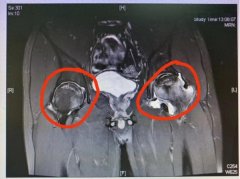

股骨头

• 白酒半斤、啤酒七八瓶!男子长期喝酒致股骨头坏死

股骨头 余敏 坏死 2024/10/21